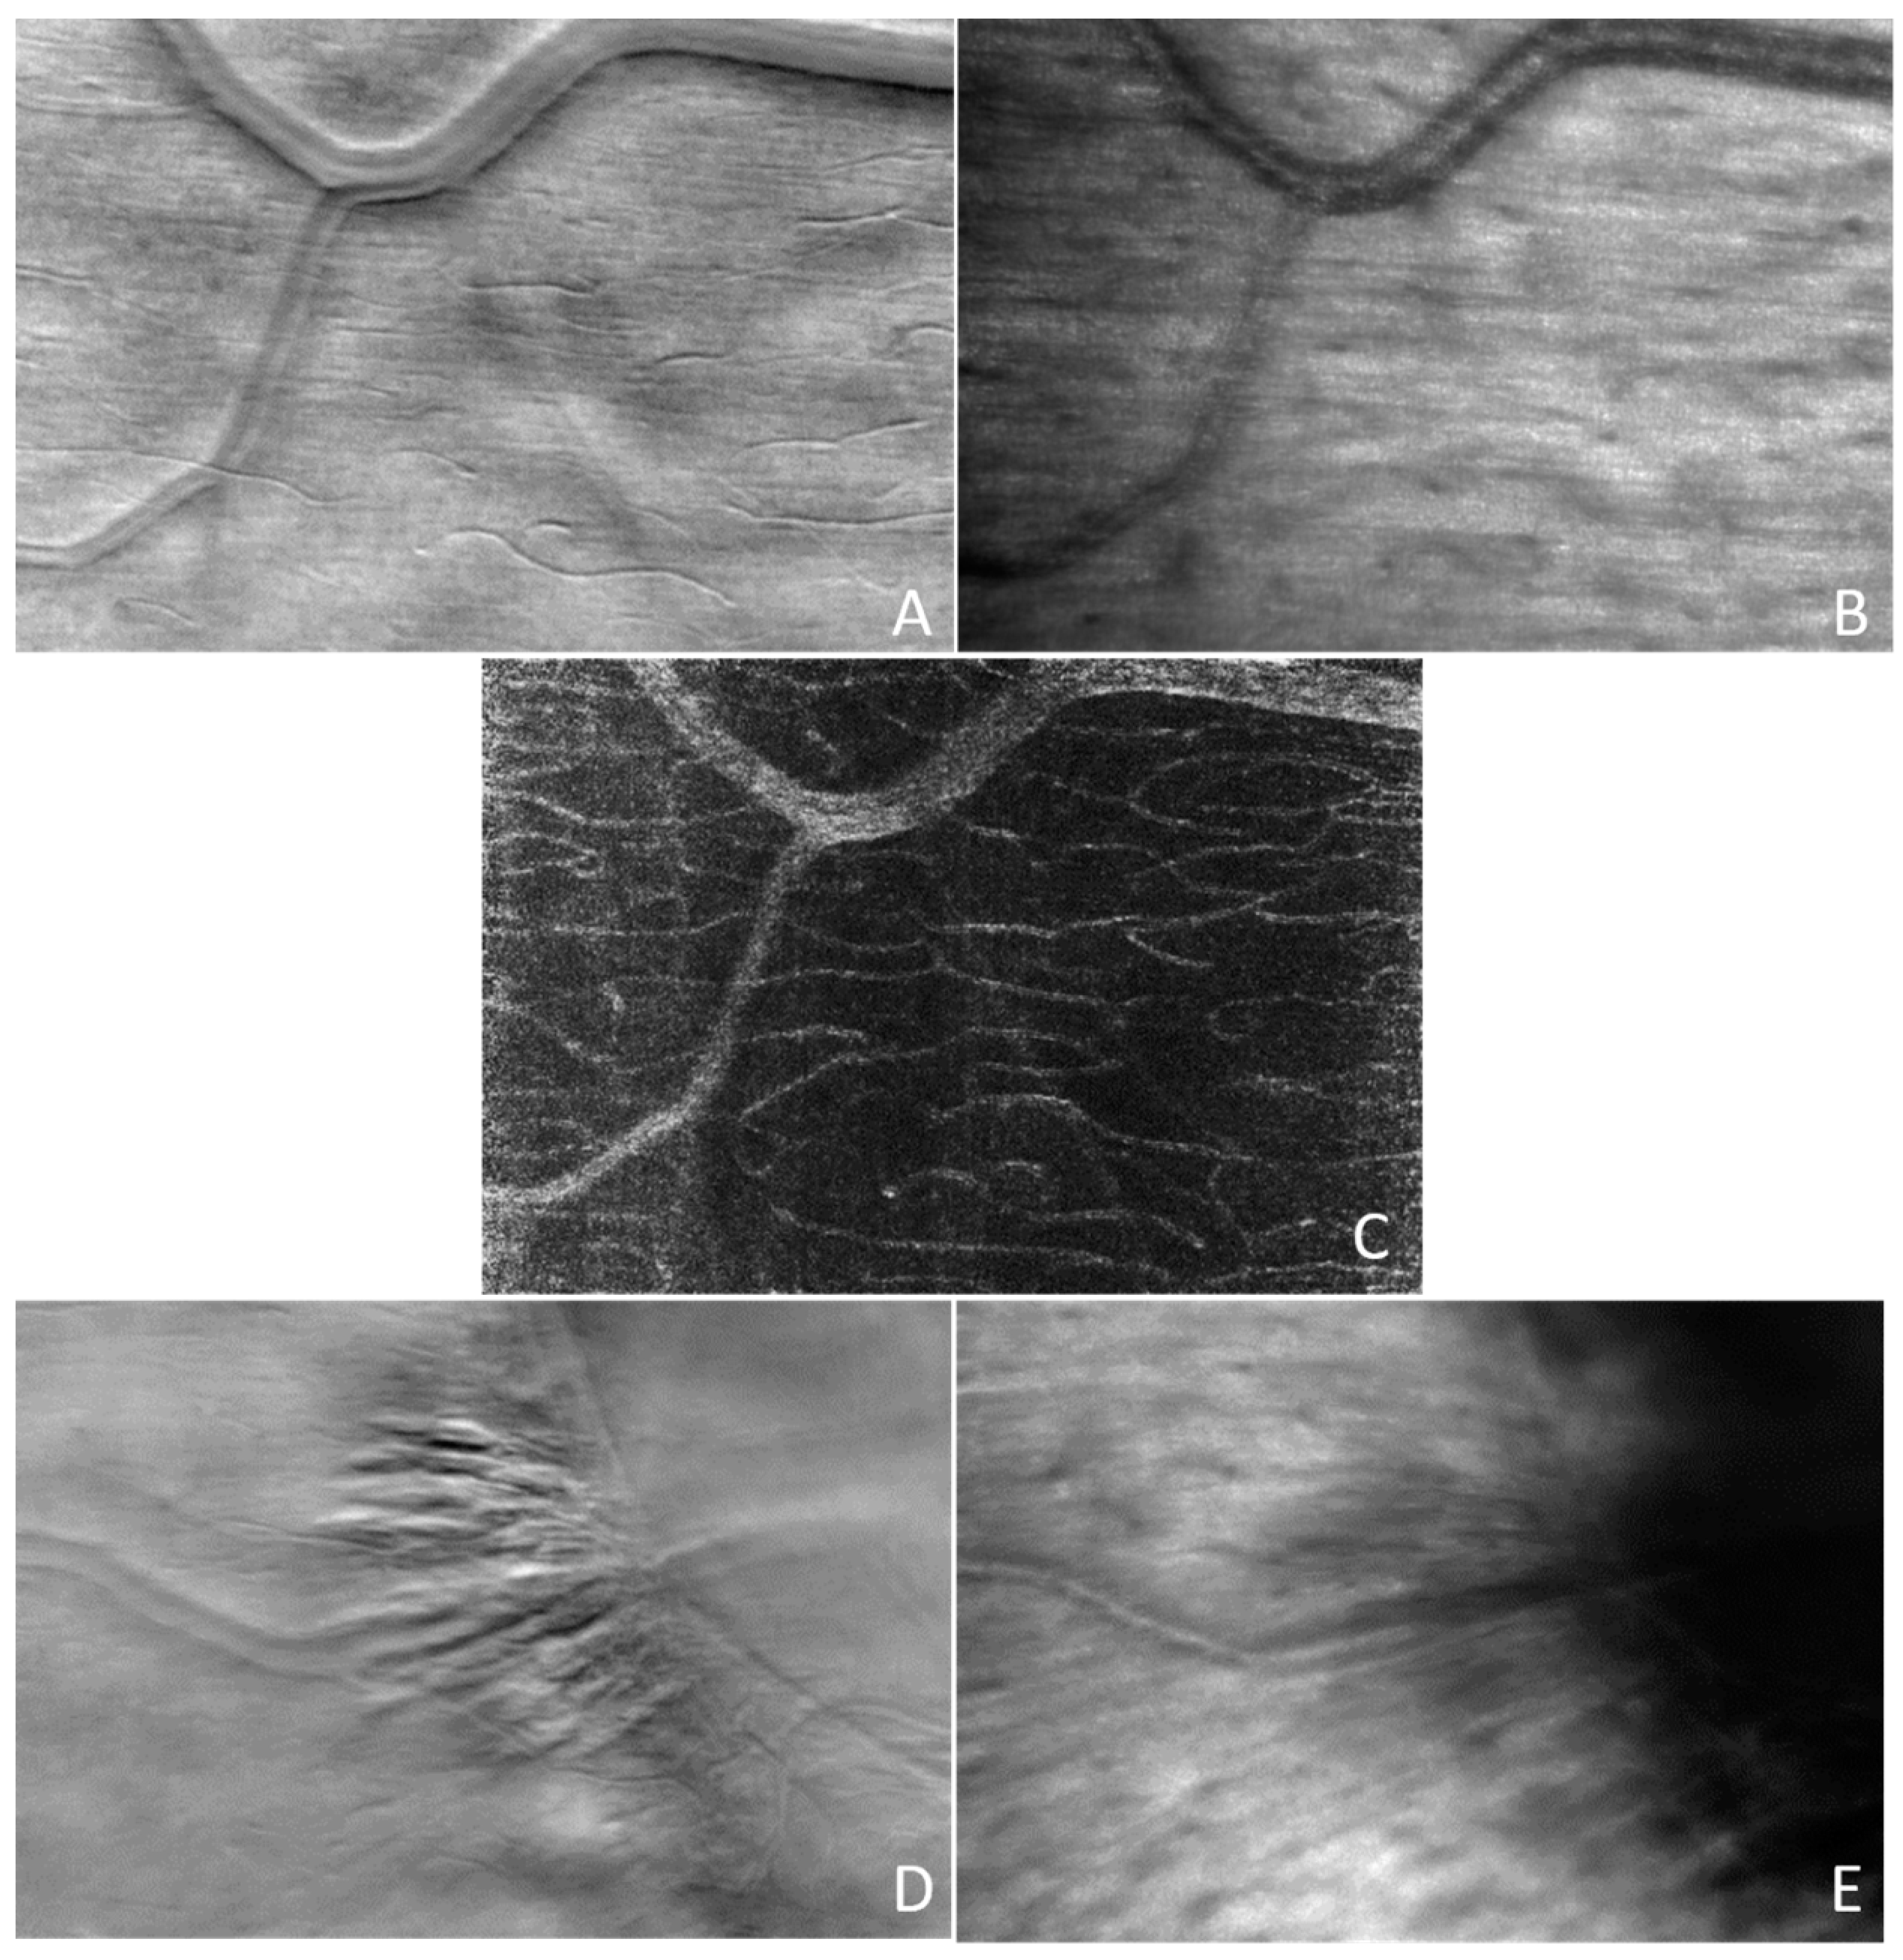

Figure 16 shows examples of the split-detection images (A and D), bright-field confocal images (B and E), and STD image (C). The top line and the center images (A, B, and C) are at the same location, while the bottom line is at the edge of the optic nerve head (ONH).

The second version of CAORI used a TDI camera for offset aperture imaging in addition to the confocal camera. The TDI camera enabled integration over a thick band shifted from the line illumination that was imaged with the confocal line camera. Two bands above and below the line illumination were projected side by side on the TDI camera and were recorded simultaneously, providing two offset aperture images and, therefore, the split-detector image. Figure 16 shows examples of the SPL and confocal AO-LSO images. Panel A shows the detailed structure of a blood vessel wall and the location of several capillaries in the SPL image, while panel B shows the nerve bundles in the confocal image. The STD image in panel C significantly increases the contrast, illustrating the capillaries not visible in the split-detection or the confocal image. As expected, however, vertical edges are not well resolved since the split direction is vertical, perpendicular to the horizontal line illumination. The bottom row of Figure 16 shows in the split-detection image (D) detailed structures at the edge of the ONH not visible in the confocal image (E). The confocal image shows nerve bundles converging into the ONH. The ONH is on the top-right side of these images.